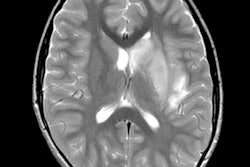

The current case study from Allegheny Health Network Stroke Center in Pittsburgh is of a 64-year-old man who presented to the emergency department after waking up at home with symptoms of left-sided paralysis and shortness of breath. He had tested positive for COVID-19 16 days prior and was recovering well before his sudden onset of ischemic stroke. The patient passed away from complications of COVID-19 three days after admission to the hospital.

Image A: Noncontrast CT on the day of admission demonstrates subtle findings of acute ischemia in the right middle cerebral artery (arrowheads) and bilateral anterior cerebral artery (arrows) territories, including hypoattenuation and loss of gray-white differentiation. Image B: Repeat noncontrast CT on hospital day two demonstrates progression of acute infarcts in the right middle cerebral artery and bilateral anterior cerebral artery territories, including worsening edema and mass effect. Image courtesy of AJNR.Data about COVID-19 gathered around the world suggests 5% to 6% of patients with severe cases may suffer a cerebrovascular injury.

"What's unique with our case is that the patient represented a subgroup where a stroke may occur in someone with atypical symptomatic onset," said Dr. Michael Goldberg, a neuroradiologist and director of the Allegheny Health Network Division of Neuroradiology.